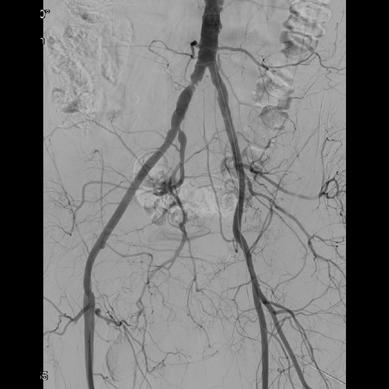

The focus of their study was to establish the role of IR in the management of potentially lifethreatening postpancreatectomy complications such as PPH, thus preventing re-exploration. To do so, Kulkarni and colleagues enrolled 758 patients who underwent pancreatic surgery between January 2014 and December 2019. All patients who developed post-surgical complications within 90 days of primary hospitalisation were included. Complications were classified according to the International Study Group of Pancreatic Surgery (ISGPS).

The types of surgery included in the study were pancreatectomy (4%), pancreaticoduodenectomy (73.8%), enucleation (1%), pancreatectomy and vein resection (4.85%), and multivisceral pancreatic surgery (16.5%). Of the 758 patients included, 206 (27.2%) developed post-surgical complications. Of these, 46 patients (6%) experienced PPH, with 30 patients (3.96%) requiring intervention; 13 patients (43.3%) underwent angioembolization, of whom five (38.46%) died due to causes unrelated to PPH, while 17 patients (56.7%) underwent surgical reexploration.

The authors note that the 90-day mortality rate in patients with PPH was 17.39%, which is comparable

with other studies in the literature. For patients who underwent primary angioembolization for PPH, the mortality rate was 38.46%—which is not statistically significant, they detail. The causes of death for these five patients included biliary sepsis with multiorgan dysfunction, myocardial infarction, hepatic decompensation, and major hepaticojejunostomy and pancreatojejunostomy leaks. Kulkarni and colleagues state that “although PPH may have been a contributing factor, the causes of death were not directly related to the condition”.

“These five patients who underwent re-exploration were beyond the scope of management by IR,” state Kulkarni and colleagues, who explain that mortality rates in patients with PPH “remain high despite aggressive intervention”. They do note, however, that these patients also tend to have associated complications and comorbidities which contribute to increased mortality and morbidity rates. They describe that common comorbidities among this patient population are diabetes, hypertension, hypothyroidism and coronary artery disease; 45 patients in their study cohort presented with one comorbidity and 47 with multiple.

“Image-guided interventions successfully prevented re-exploration in 61.5% of PPH cases, 88.9% of biliary complications, and 99.3% of intra-abdominal fluid collections,” state Kulkarni et al, emphasising the “pivotal role” IR plays in managing post-surgical complications.

“IR provides a minimally invasive alternative to surgical re-exploration, reducing recovery time and preventing morbidity associated with re-exploration,” say the authors. They highlight that “early recognition and prompt intervention” are key in patients with PPH, biliary leak and portal vein thrombosis, as these are conditions associated with high mortality and morbidity rates. However, in cases where surgical re-exploration is required, this is “often due to complications which are beyond the scope of percutaneous management”, Kulkarni et al point out.

“Despite the success of IR procedures, some patients may still require reoperation in situations such as anastomotic dehiscence, or peritonitis. Moreover, increased frequency of complications is associated with a higher risk of mortality,” the authors state.

Finalising thoughts on the present findings, Kulkarni and colleagues conclude that IR procedures are safe and effective, and represent a cooperative, minimally invasive approach to managing postpancreatectomy complications, to “reduce recovery time and prevent morbidity associated with re-exploration”.